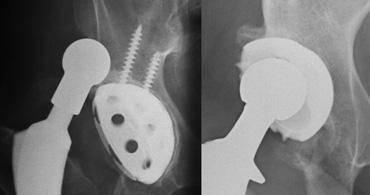

LEFT: Revision THA with a large femoral stem with periprosthetic fracture.RIGHT: Cement extrusion intrapelvic through acetabular defect.

Gãy xương quanh khớp nhân tạo

Gãy xương có thể xảy ra sau phẫu thuật ở những bệnh nhân có chất lượng xương kém và sử dụng khớp nhân tạo thay thế có cán dài, hoặc khi giải phẫu bất thường như trong trường hợp loạn sản khớp háng hoặc đã từng phẫu thuật trước đó.

Gãy xương cũng phổ biến hơn với các cán xương đùi không xi măng, vì các loại này phải vừa khít chính xác và có thể gây gãy xương trong quá trình đặt khớp.

Tỷ lệ gãy xương dao động từ 0,1 đến 1,0 phần trăm đối với các thành phần có xi măng và từ 3 đến 18 phần trăm đối với các thành phần không xi măng. Hầu hết các trường hợp gãy xương trong phẫu thuật xảy ra ở phía xương đùi.

Tràn xi măng ra ngoài

Khi ổ cối được chuẩn bị để đặt cốc, có thể xảy ra thủng. Khiếm khuyết này được lấp đầy bằng mảnh xương, xi măng hoặc ghép xương.

Tràn xi măng ra ngoài thường không có triệu chứng.

Các biến chứng hiếm gặp bao gồm rò ruột, bao bọc các cấu trúc mạch máu thần kinh và bỏng thành bàng quang.